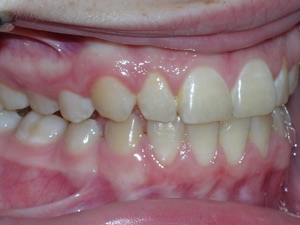

Here’s a fascinating case of a young lady who had a completely blocked out premolar.

With a combination of braces, expansion and trimming we were able to bring it in. Watch!

Here are the results.